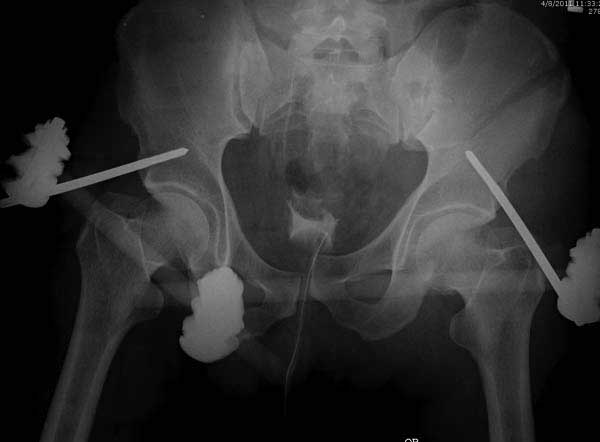

Здесь представлен случай 38 летнего больного (падение с высоты 9 метров) с нарушением тазового кольца. При поступлении для стабилизации передне-нижний аппарат наружной фиксации и на 6й день, вчера, операция из двух доступов.

Наружные фиксаторы создают не только стабильность костей таза, а также в экстренных случаях помогают уменьшить обьем таза в профилактике кровотечения!

Представлены снимки техники проведения стержней. Через место прикрепления прямой мышцы в Inferior Iliac Spine в направления вырезки создается жесткость. Weber clamp изнутри таза для репозиции, и фиксация после репозиции перелома крыла подвздошной кости. Наружный аппарат удален, нагрузка предполагается через два месяца.